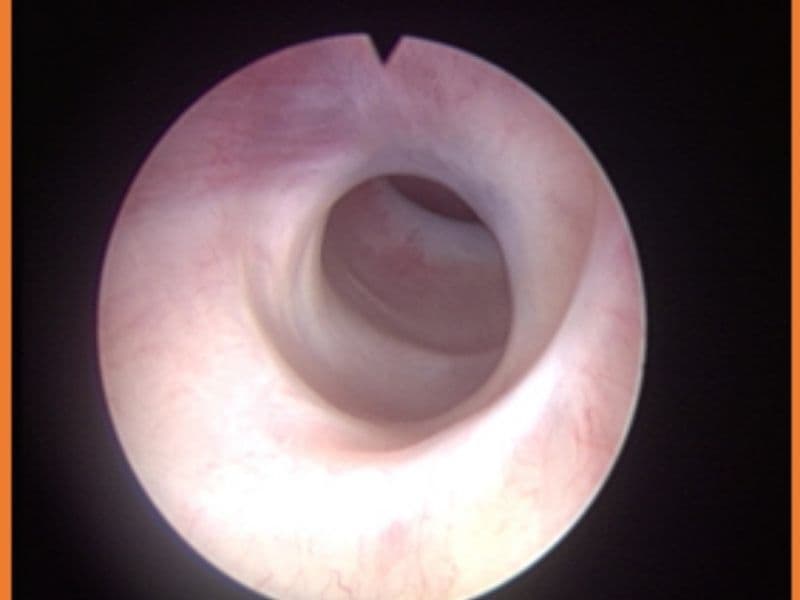

- Endoskopik inceleme (sistoskopi/üretroskopi) (kamera ile idrar yoluna bakılır)